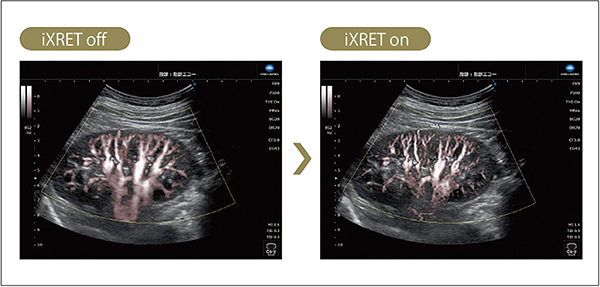

フレームレートを維持しながら分解能を向上する技術として,iXRET(eXtended Resolution Enhancement Technology)を搭載した。機械学習を活用して構築した独自の画像処理技術により,従来のリアルタイム性能向上技術では課題となっていたアーチファクトを抑えながら,少ない音響線数で取得された超音波画像の解像度向上を実現した。iXRETは,Bモード画像とカラードプラ画像の両方に適用可能であり,特にカラードプラ画像では,ノイズと血流の判別能が上がり,微細な血流の視認性が向上した画像を提供可能となった(図3)。

図3 iXRETの効果